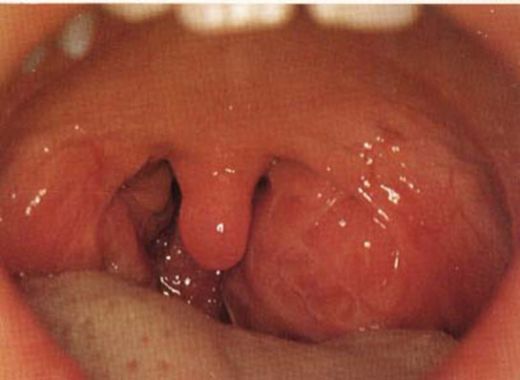

Sol bademcik şişmesi neden olur? Bu durumun birçok sebebi olabilir. Viral enfeksiyonlar, bakteriyel enfeksiyonlar ya da alerjik reaksiyonlar bademciklerin iltihaplanmasına yol açabilir. Belirtiler arasında boğazda ağrı ve yutma zorluğu yer alır. Tedavi yöntemleri ise altta yatan nedene bağlı olarak değişir.

Sol bademcik şişmesi gerçekten de birçok farklı nedenden kaynaklanabilir. Enfeksiyonlar, özellikle viral ve bakteriyel olanlar, bademciklerde iltihaplanmaya yol açabilir. Ayrıca, alerjik reaksiyonlar da bu durumu tetikleyebilir. Belirttiğin gibi, boğazda ağrı ve yutma zorluğu gibi belirtiler genellikle eşlik eder.

Tedavi Yöntemleri ise, şişmenin nedenine bağlı olarak değişiklik gösterir. Eğer viral bir enfeksiyon söz konusuysa, genellikle dinlenme ve bol sıvı tüketimi önerilir. Bakteriyel enfeksiyonlar için ise, doktorun önerisi doğrultusunda antibiyotik tedavisi gerekli olabilir.

Sol bademcik şişmesi yaşadım ve gerçekten rahatsız edici bir durum. Boğazımda ağrı ve yutkunma güçlüğü ile birlikte beyaz lekeler oluştu. Tedavi için doktora başvurdum. Tek taraflı bademcik şişmesi doktor sitesinde de belirttiği gibi önemli bir durum, dikkat edilmesi lazım.

Alpartur, yaşadığın bu durum gerçekten de rahatsız edici olabilir. Boğazdaki ağrı ve yutkunma güçlüğü, günlük yaşamı olumsuz etkileyebilir. Beyaz lekelerin varlığı, enfeksiyon belirtilerine işaret edebilir ve bu nedenle doktora başvurman çok önemli bir adım.